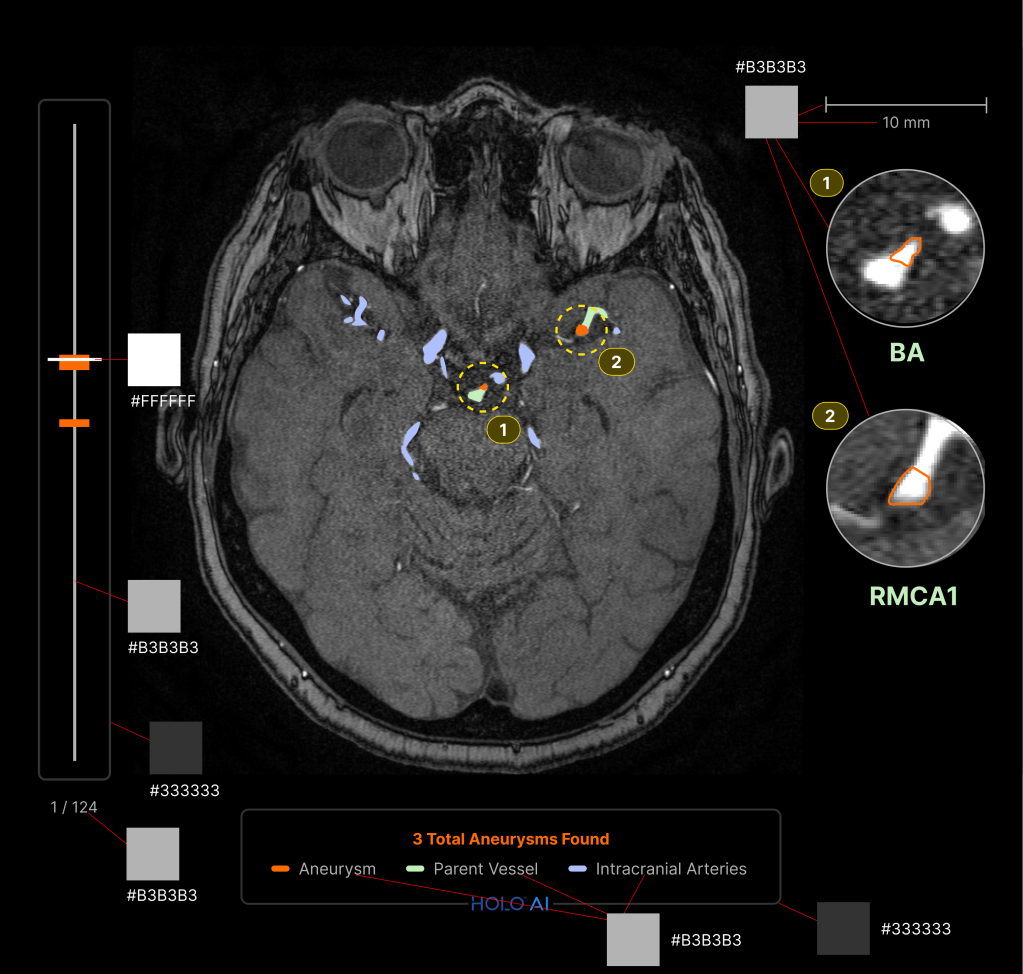

A similar process started in parallel to create AI-enriched DICOM images for an application in aneurysm. I used a similar approach and conducted weekly design critiques with physicians in order to refine the designs.

Developer Handoff

The final step in implementing the designs in our product would be to equip our development team with the visual criteria and visual assets. In addition to detailed mockups such as the one below, I presented an interactive Design Systems in-depth technical presentation that taught our front-end developers how to interact with our Figma design system and pages.